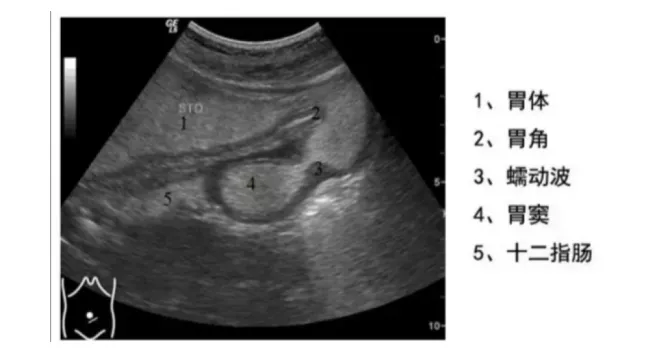

于长路主任说 , 胃肠充盈超声造影检查 , 是通过一种造影剂充盈胃肠腔的检查 , 该类造影剂充盈胃肠腔后在声像图上显示类似于实质性组织的回声 , 消除了胃腔内的气体及黏液干扰 , 和胃肠壁及肝、胆、脾、胰之间产生明显的对比效应 , 清晰地显示胃肠壁的层次结构 , 从而使胃肠内腔产生良好的声学造影效果 。

【造影剂|胃肠也能做B超?专家:有其特有优势,适合七大类情况】·可实时、多次从不同角度对胃肠进行扫查,同时观察胃张力、蠕动及排空情况 , 并适合进行长期随访、复查 。